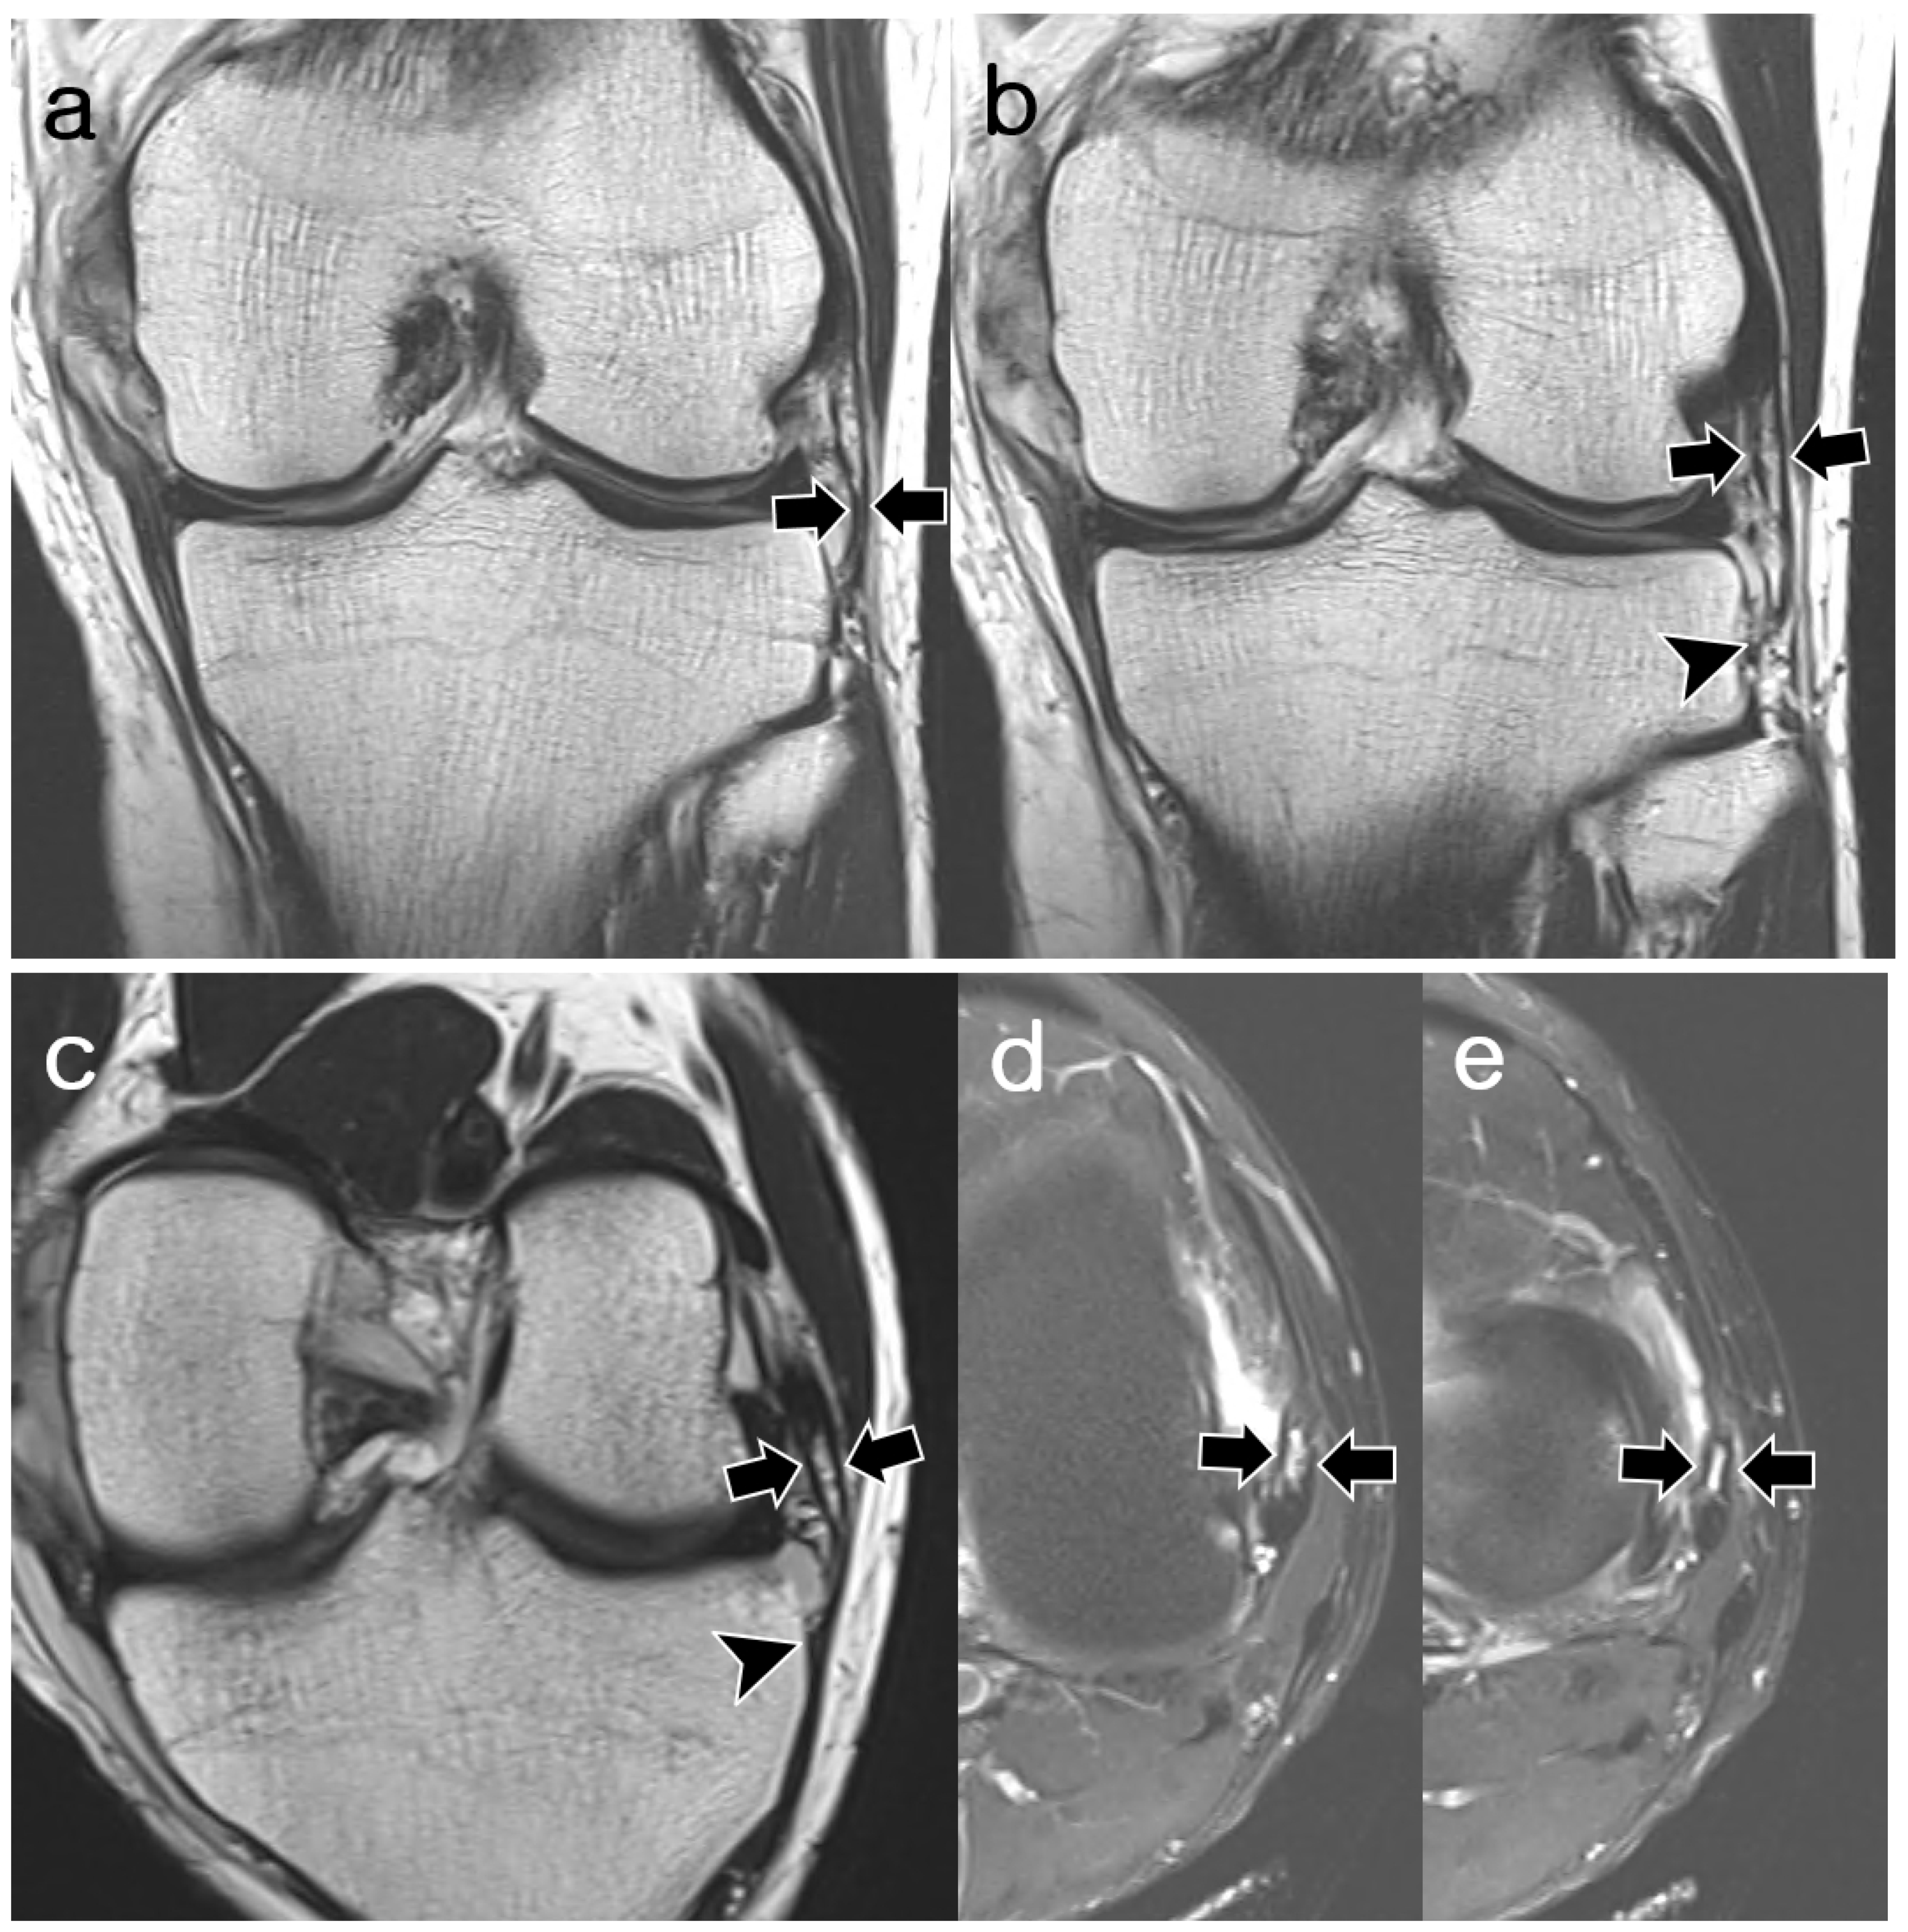

3.2. ALL Visibility

3.3. ALL Morphology